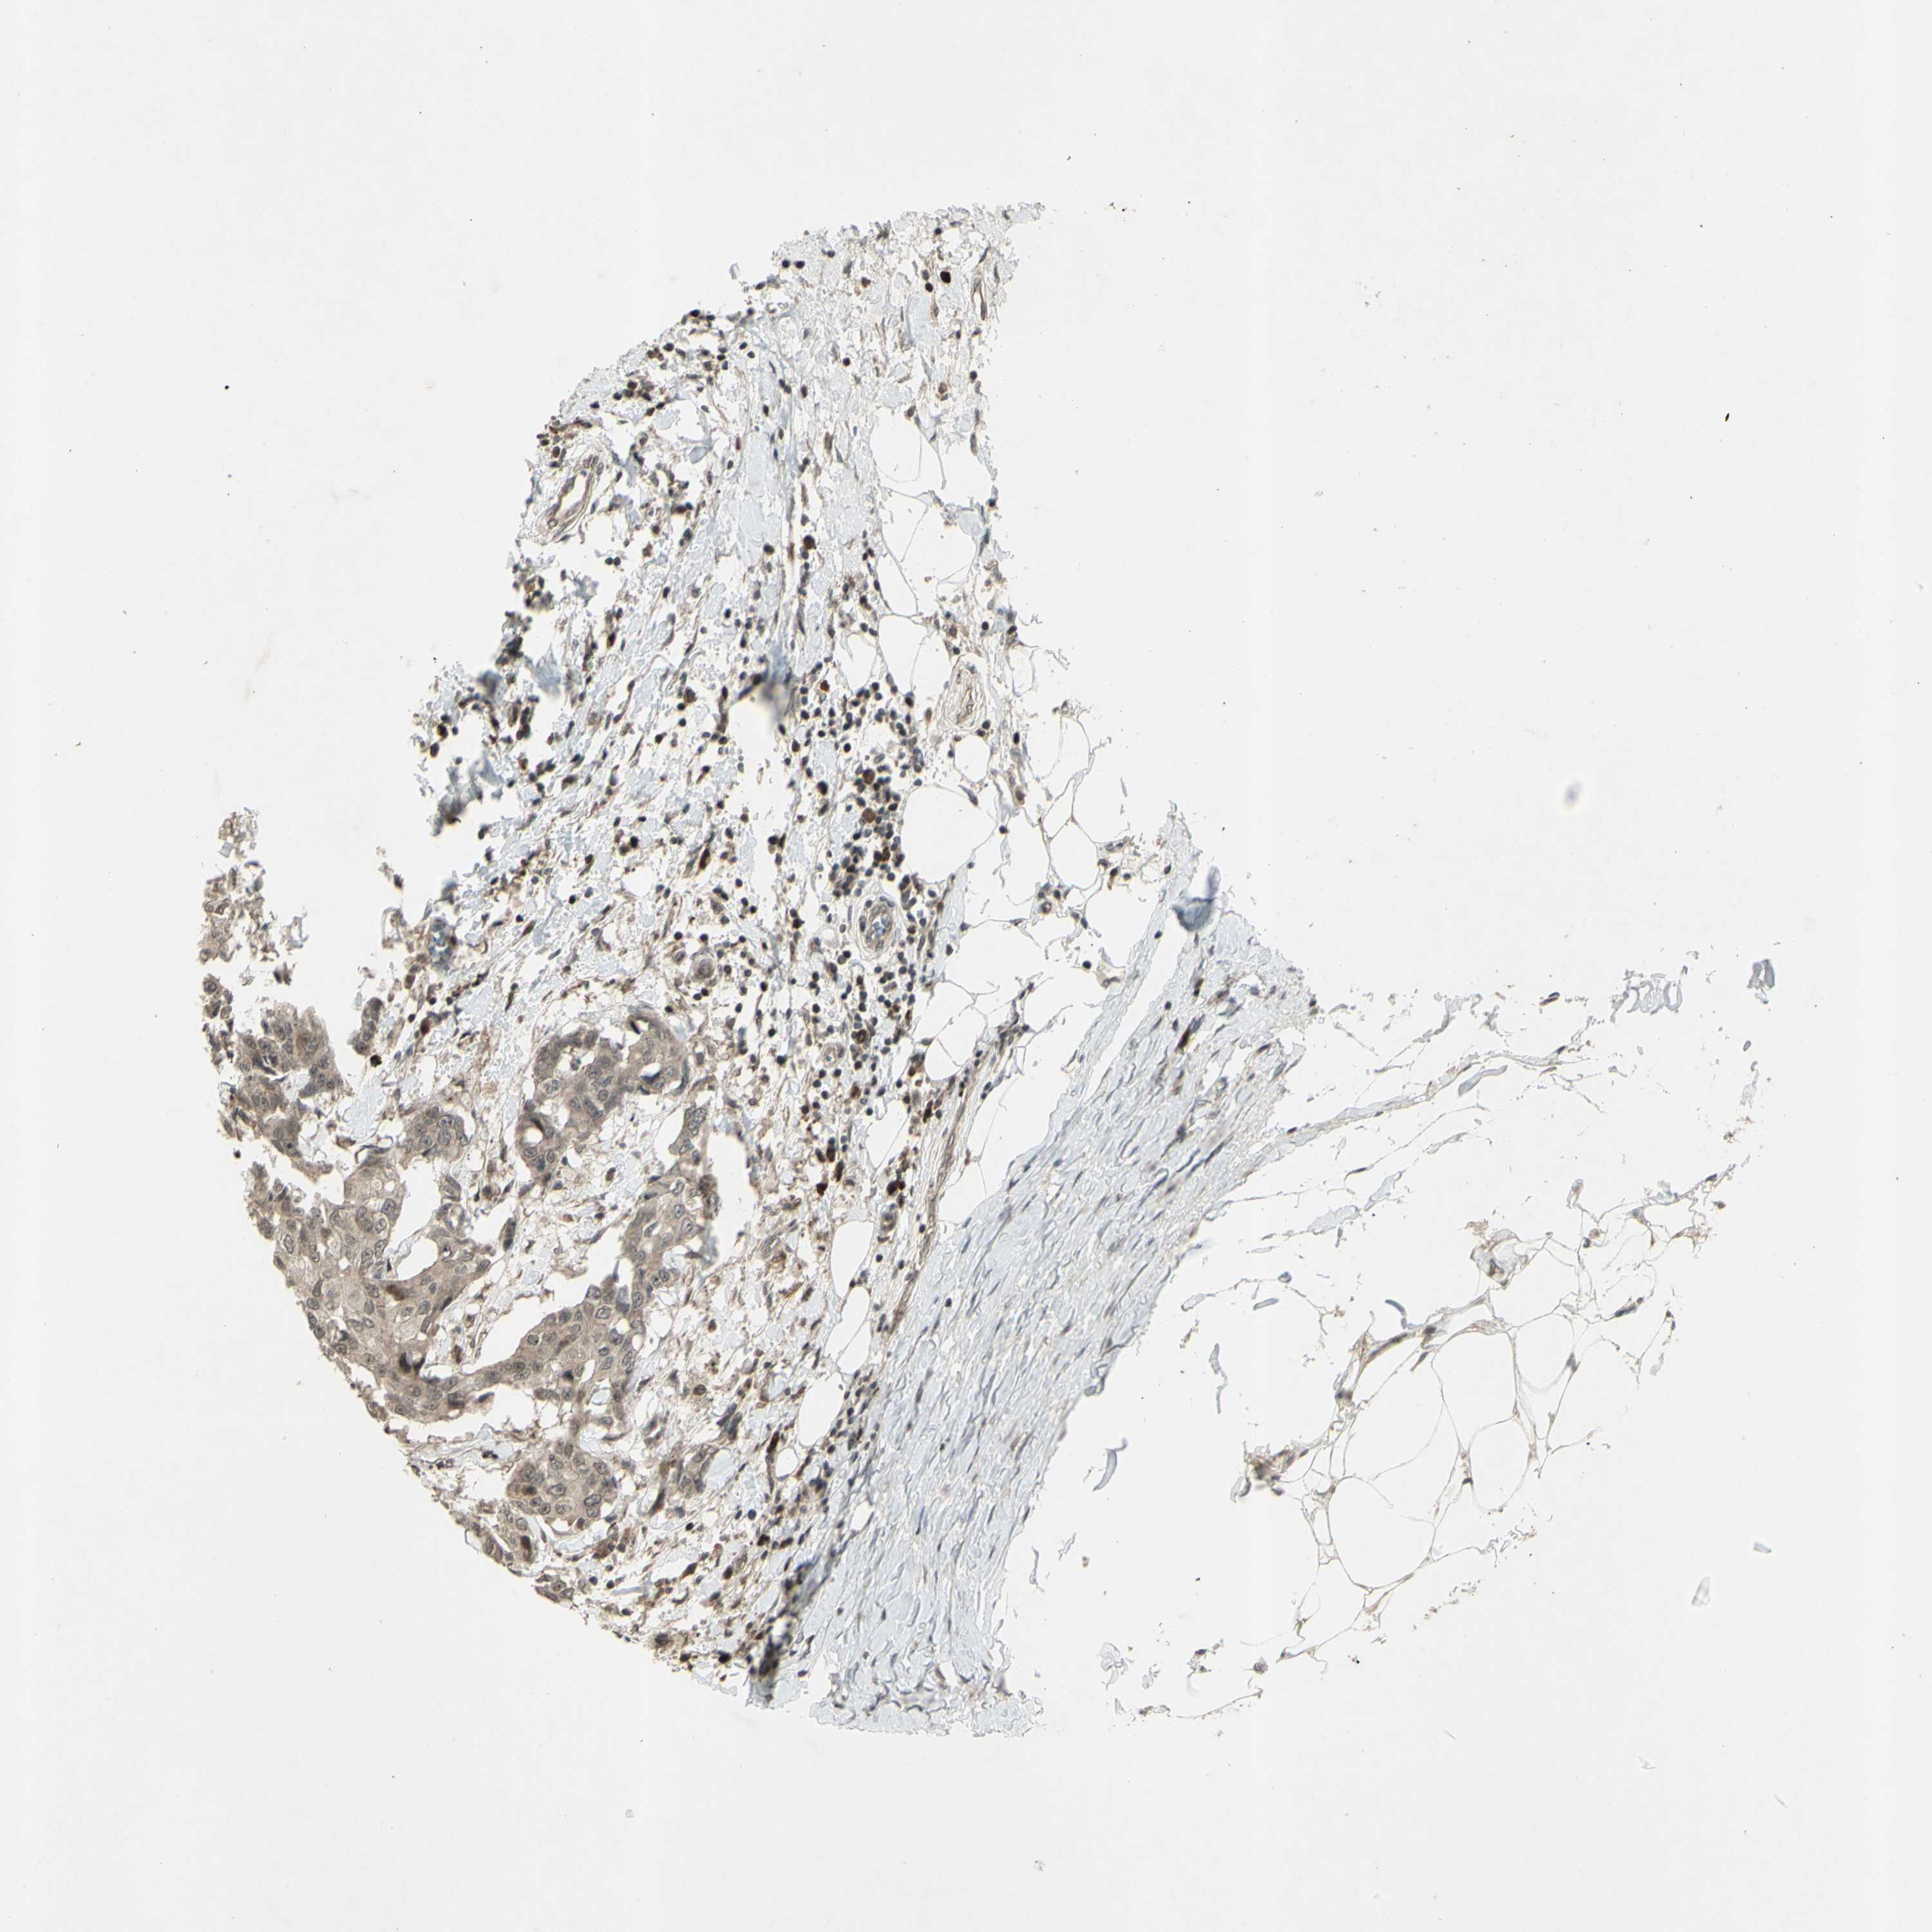

CANCER BREAST CANCER Show tissue menu

BRCA TCGA BRCA VALIDATION PROTEIN EXPRESSION